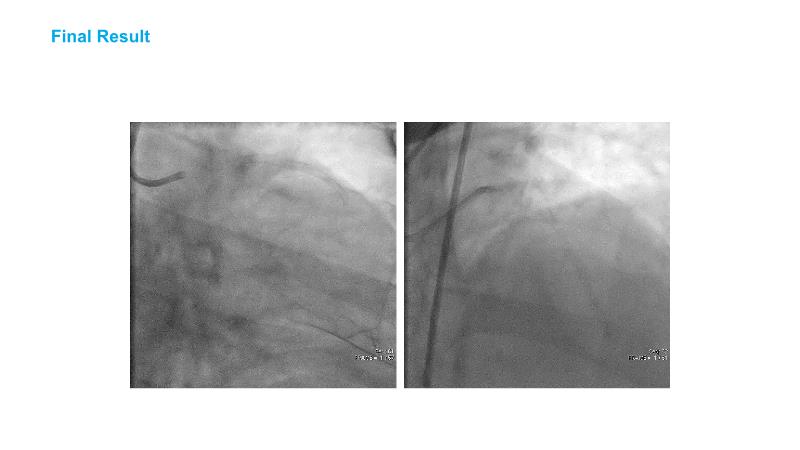

Over the last five years, we have learned that there is a new tool for treating calcium, the greatest enemy of interventional cardiology, which can take various forms: intravascular lithotripsy. In this session, look at how to master this technique in different scenarios, from eccentric calcified lesions to left main bifurcations.

- To understand the mechanism of action of intravascular lithotripsy (IVL) for the treatment of calcified lesions